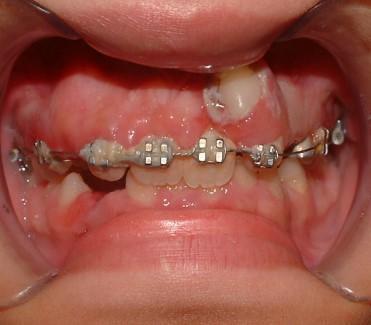

Στην συγκεκριμένη περίπτωση η παρουσία οδοντωμάτων εμποδίζει την ανατολή των μόνιμων κεντρικών τομέων καθιστώντας τα έγκλειστα.

H έγκαιρη παρέμβαση λύνει το πρόβλημα με την χειρουργική απομάκρυνση των οδοντομάτων και με την υποβοηθούμενη μετατόπιση των κυρίως δοντιών με ορθοδοντικές δυνάμεις.